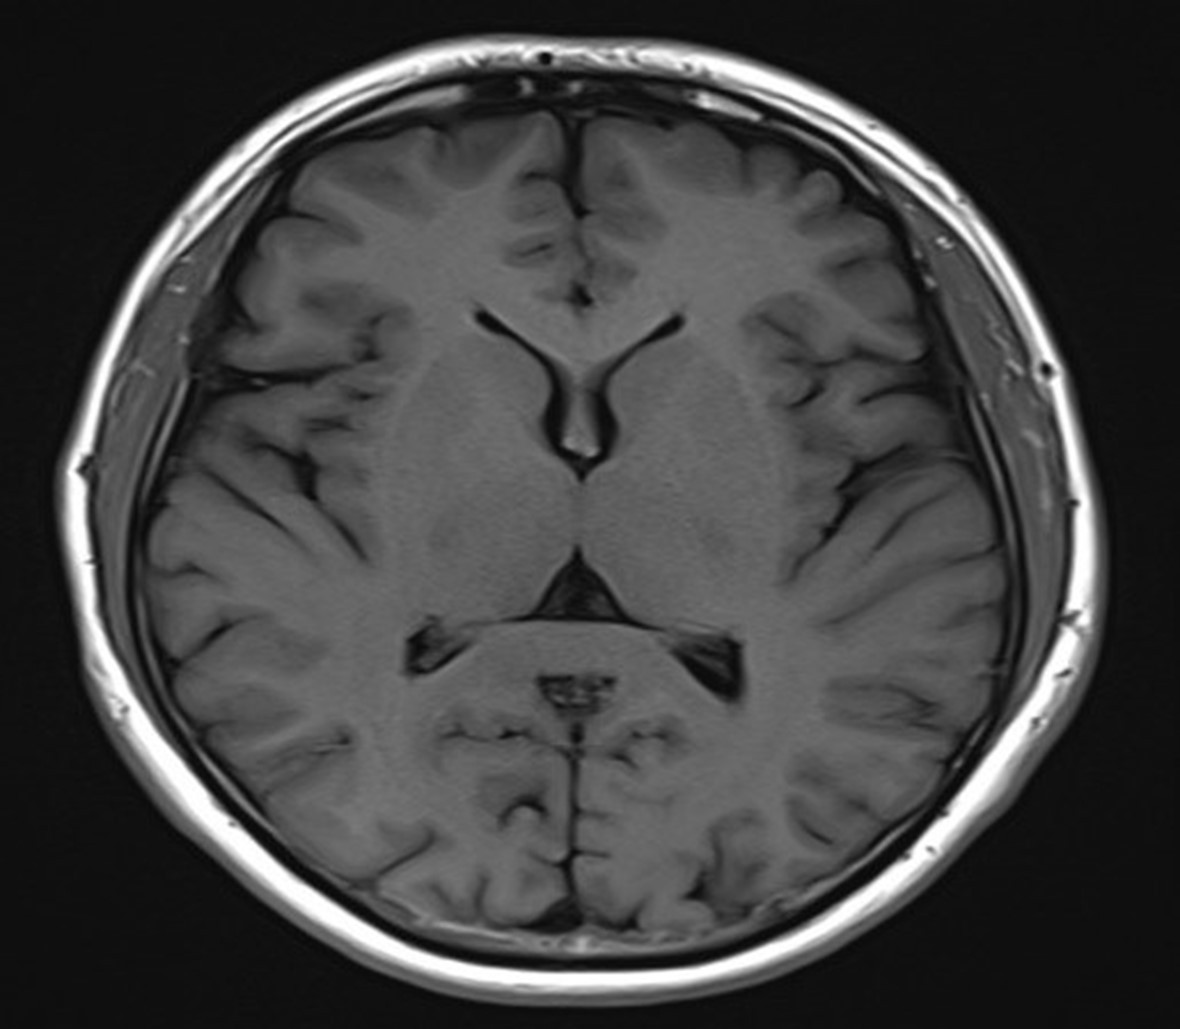

그림4.jpg 촬영 일시: 2025.07.11

<Fig 1. 뇌 MRI>

뇌 자체에는 아무런 문제가 없었지만

자율신경 기능에 이상 소견이 나타났거든요.

이 환자분의 갑작스러운 어지럼증은

단순한 이석증이나 메니에르병이 아니라

목 디스크로 인한 자율신경계 이상이 원인이었던 거예요.